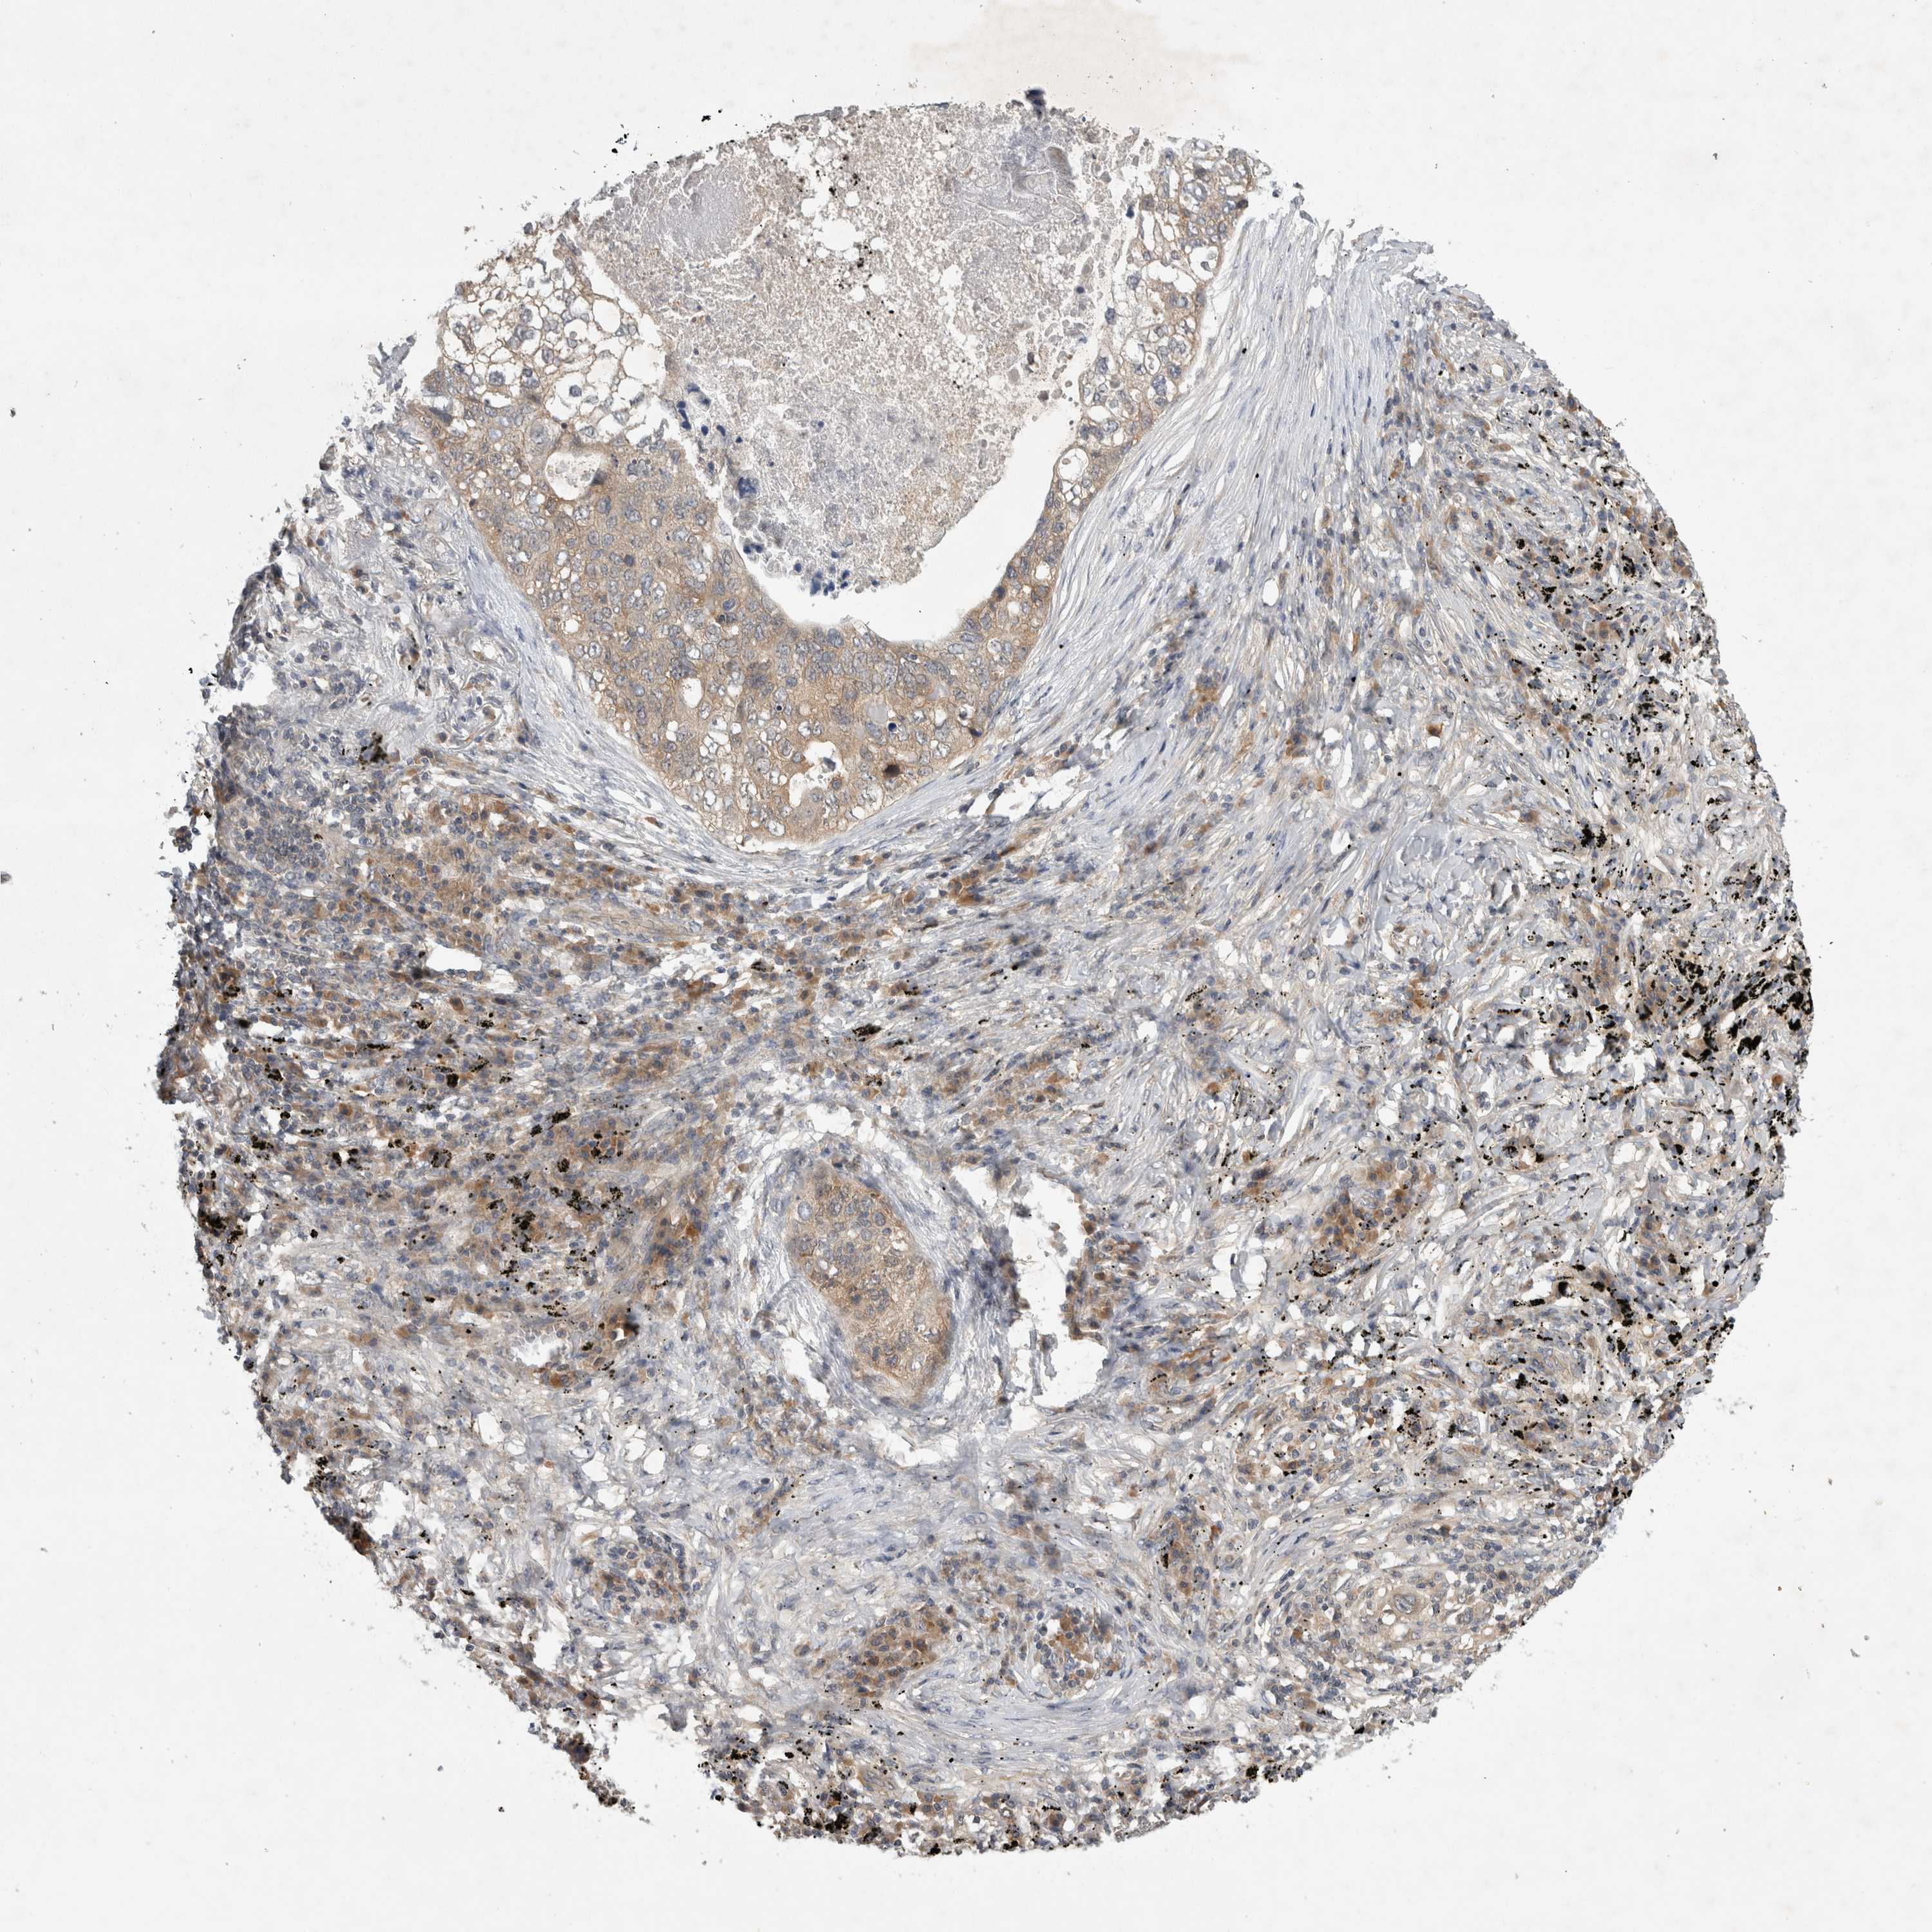

CANCER LUNG CANCER Show tissue menu

LUAD TCGA LUAD VALIDATION LUSC TCGA LUSC VALIDATION PROTEIN LUAD CPTAC PROTEIN LUSC CPTAC PROTEIN EXPRESSION